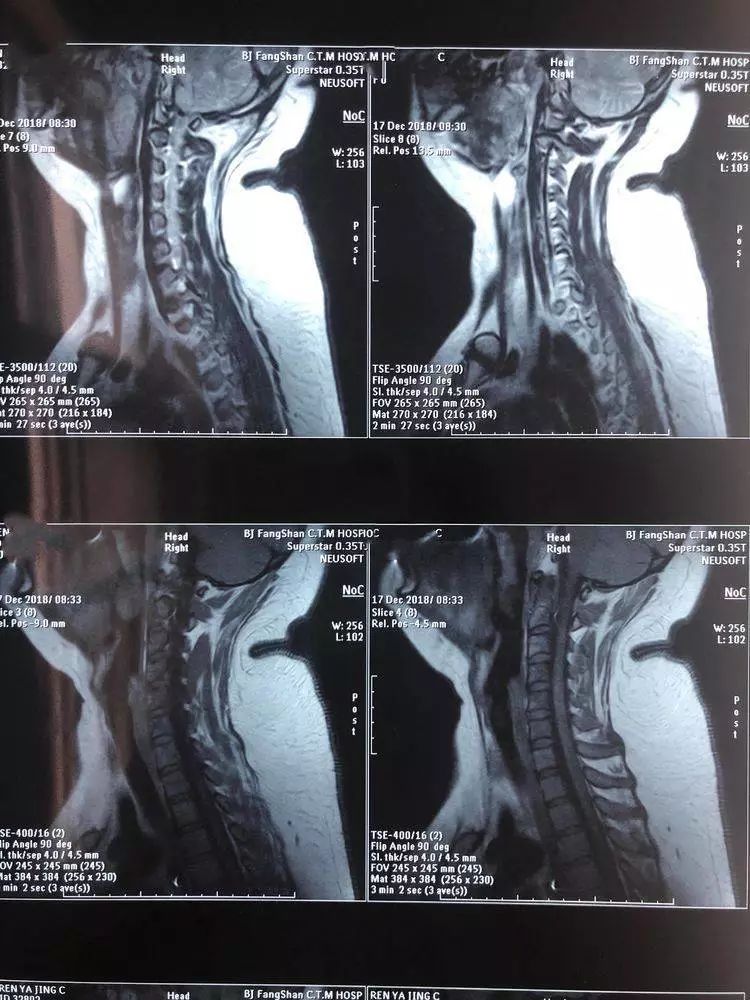

核磁下的"富贵包"

为了解释这个问题,我们来看看女孩的背部x光片.